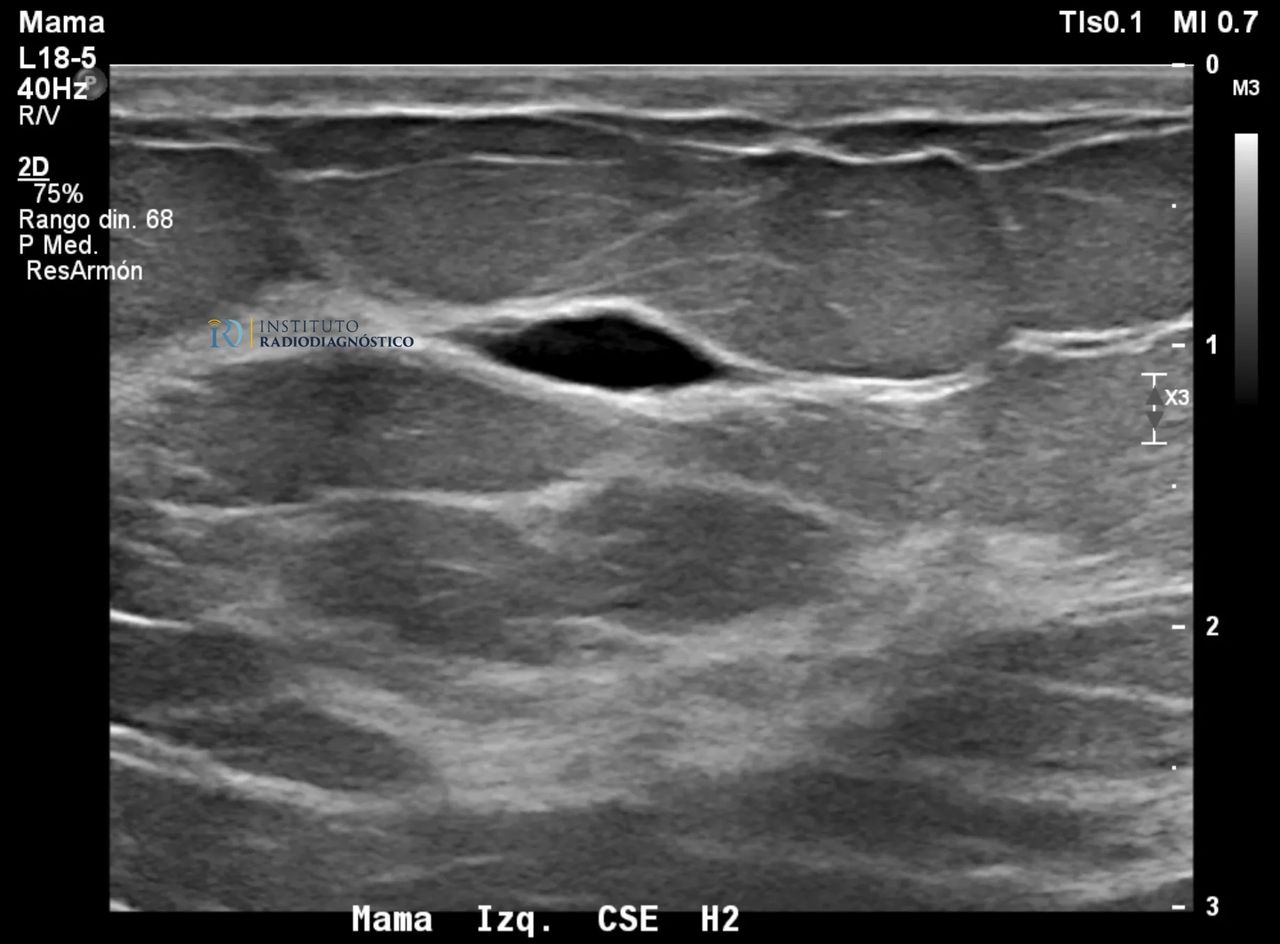

Qué son los quistes mamarios y cómo se manejan?